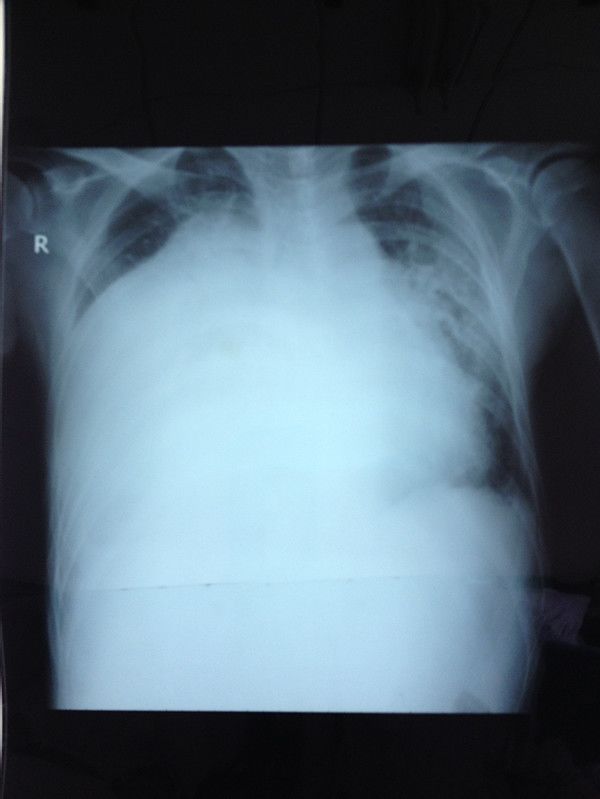

胸片

右心衰:右室大,左室小,左室呈D形,少量心包积液

Rudski LG, et al. J Am Soc Echocardiogr 2010;23:685–71